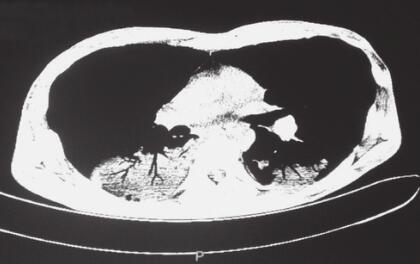

入院后检查:消瘦,双肺呼吸音减弱,未闻及干湿性啰音,无胸膜摩擦音。复查胸部CT示(图1):双下肺大片状实变影。2013年11月6日血常规示:WBC 15.02×109/L,HGB 82g/L。肝肾功能未见明显异常。入院后诊断:①肺部感染(结核?真菌?);②机化性肺炎?加用吡嗪酰胺四联抗结核,给予莫西沙星抗感染,伏立康唑抗真菌治疗。但患者仍有发热,最高体温达40℃,咳嗽、咳痰缓解不明显。于2013年11月12日在CT引导下行经皮肺穿刺术,肺组织活检病理检查结果:镜下见肺泡间隔增宽,纤维组织增生,肺泡上皮增生,肺泡腔扩张,部分腔内见胞浆空亮的泡沫状组织细胞,特殊染色示PAS(-),抗酸(-),六胺银(-)。

图1 2013年11月6日胸部CT(A.肺窗,B.纵隔窗)

双下肺斑片影,内有明显支气管充气征象,边缘可见磨砂玻璃样大小不一的结节状病灶